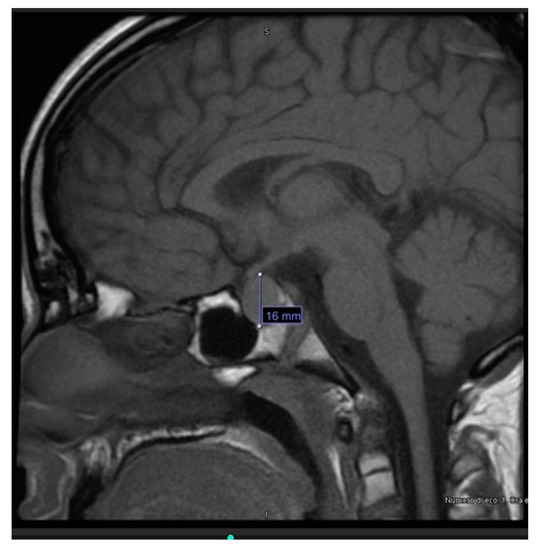

Pediatric Myxedema Due to Autoimmune Hypothyroidism: A Rare Complication of a Common Disorder

In children, hypothyroidism usually presents non-specific symptoms; symptoms can emerge gradually, compromising a timely diagnosis. We report the case of a 13-year-old male, who was admitted to the hospital due to swelling of the torso and neck. Besides these symptoms, the child was [...] Read more.

In children, hypothyroidism usually presents non-specific symptoms; symptoms can emerge gradually, compromising a timely diagnosis. We report the case of a 13-year-old male, who was admitted to the hospital due to swelling of the torso and neck. Besides these symptoms, the child was healthy, except for a significant growth delay. Ultrasound evaluation and blood tests led to the diagnosis of myxedema secondary to severe hypothyroidism, which was due to autoimmune thyroiditis. Further investigations revealed pericardial effusion and pituitary hyperplasia, with hyper-prolactinemia. Treatment with levothyroxine led to edema regression and clinical, hemato-chemical and radiological improvement. After 6 months, growth velocity increased, although the recovery of growth already lost was not guaranteed. Brain MRI showed regression of pituitary hyperplasia. The diagnostic delay in this case was probably due to the patient’s apparent good health, and the underestimation of growth restriction. This report underlines the importance of growth monitoring in adolescence, a critical period for identifying endocrine conditions; if undiagnosed, these conditions can lead to serious complications, such as myxedema in hypothyroidism, with potential effects beyond growth on multiple organs. Full article

Show Figures

Figure 1